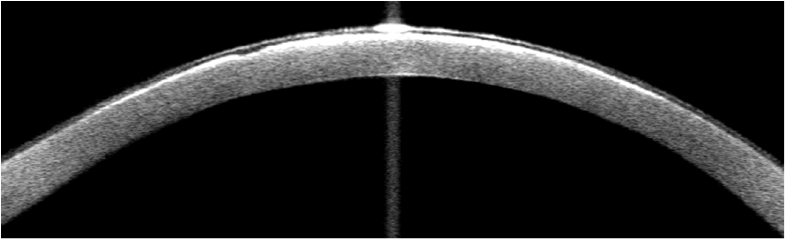

Introduction: Schnyder’s crystalline corneal dystrophy (SCCD) is a rare autossomal dominant condition characterized by abnormally increased deposition of cholesterol and phospholipids in the cornea leading to glare and disproportionate loss of photopic vision.

Results: The first case is a 60-year-old man with progressive, bilateral and painless loss of visual acuity over more than 30 years. He was clinically diagnosed with SCCD and confirmed histologically after penetrating keratoplasty. The second patient is a 41-year-old woman, daughter of the first patient, with a milder form of the disease, often more difficult to diagnose.